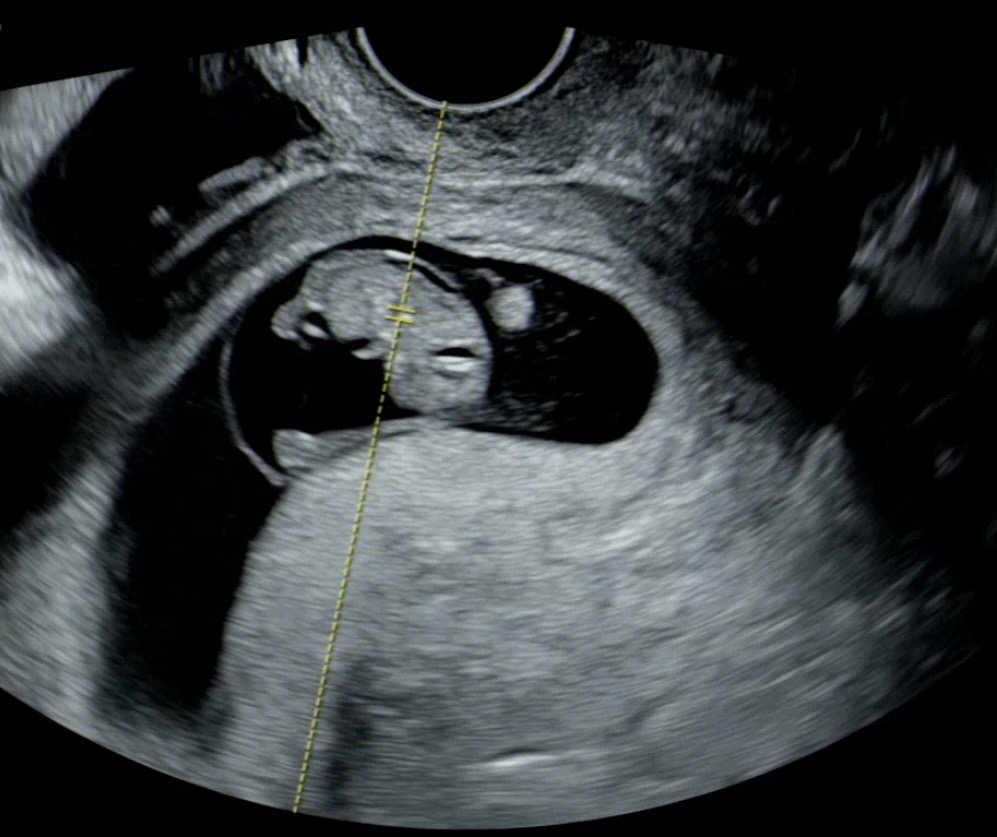

오늘 8주 5일차 인데요 젤리곰 보고싶어서 다녀왔는데 팔다리도 조굼 길쭉길쭉 생겼더라구요~ 이미 늦은건지 아나면 언제쭘가면 볼수있을까용 ㅎㅎ 헤헤…

지금이 젤리곰 시기예요. 초음파 각도에 따라 조금 다르게 보일 수 있어요.